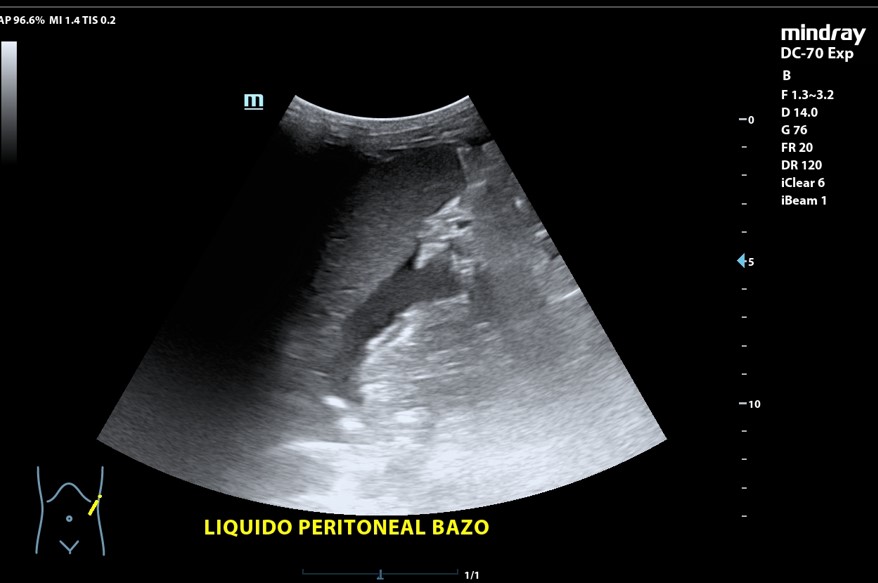

Presencia de 2 masas pélvicas bien delimitadas heterogéneas que captan Doppler, una de 5 cm de diámetro y otra ovalada de 10 cm de longitud. Líquido ascítico peritoneal, que también se observa alrededor del bazo y en espacio de Morrison. Derrame pleural derecho.